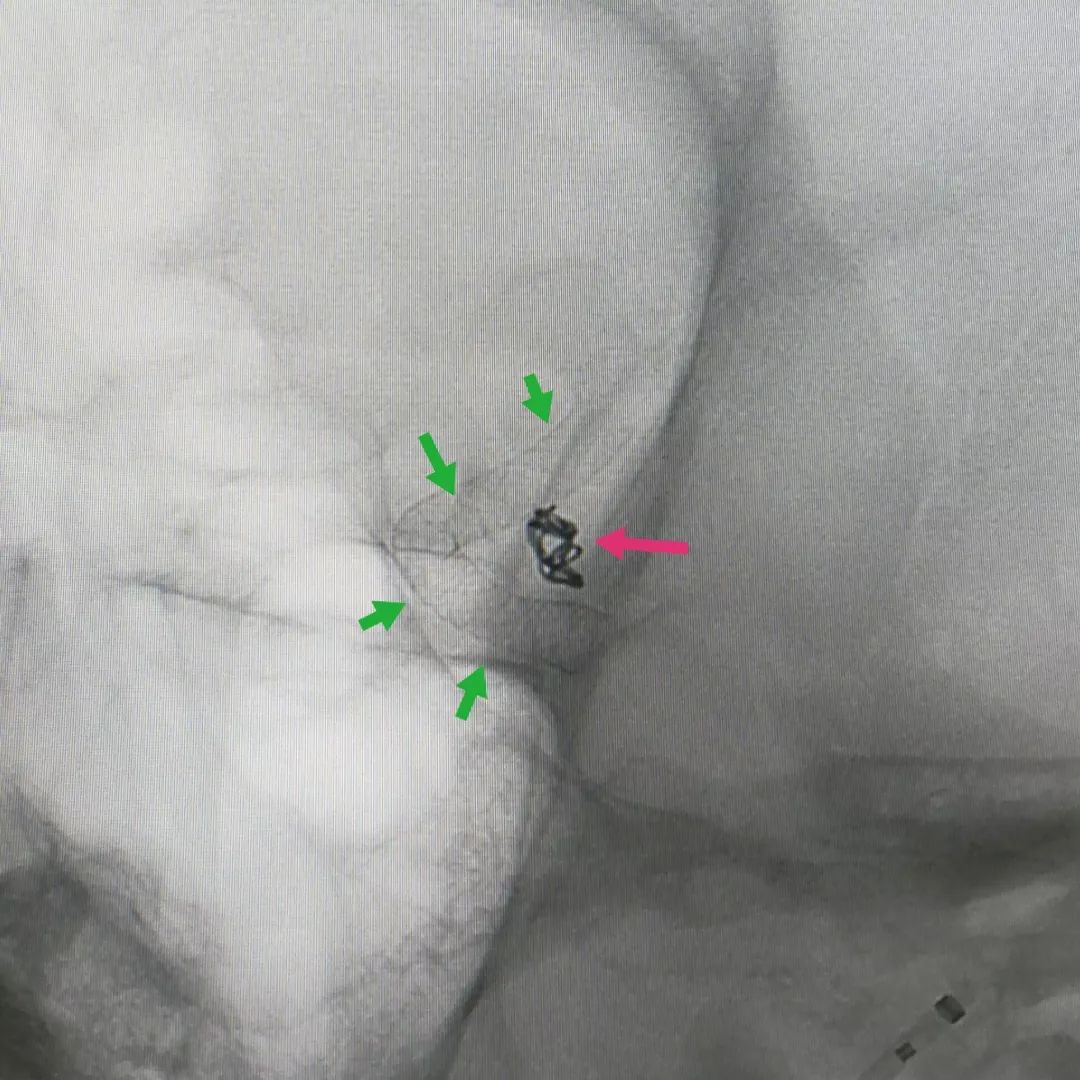

患者中年女性,头痛头晕检查发现颅内多发动脉瘤(下图绿箭头),一个位于后交通段,一个位于眼动脉段。

而且在较大的动脉瘤腔还长出了一根重要动脉血管-后交通动脉(红箭头),该动脉一旦闭塞可能会导致偏瘫甚至昏迷不醒

而且两个动脉瘤同时治疗难度和风险增加。所以我们采用了目前最先进的密网支架技术,既能保证重要血管通畅,又能彻底治愈动脉瘤。手术后可见支架完全贴合血管壁(下图绿色箭头)